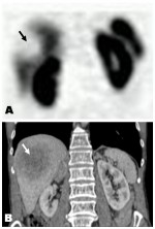

In group 1, clinical suspicions were not confirmed in any of the patients; in group 2, most of the primary lesions showed overexpression of somatostatin receptors (SSRT); in group 3, the primary tumor was not identified in any of the patients; in group 4, recurrences were depicted in 7 out of 47 patients; in group 5, only 1 malignant SPN was detected, and in group 6, regression of primary mass and metastases were seen on follow-up SRS in 1 patient.